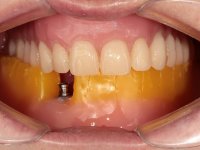

Two dental implants were planned in the CBCT scan, in the area of the inferior canines. The dental extractions were performed and, simultaneously, the alveolar crest was flattened and the implants were placed. Three issues were considered while implant placement: parallelism of the axis, same height of the implant’s neck, and same position in the coronal plan. This 3D insertion is essential to have a good retention of the overdenture in the future. Patient’s removable denture was fixed in the dental lab, to include the extracted teeth, and a soft-tissue relining was done over the healing abutments. After the osseo-integration period, a first impression was done with an open-tray and a doble-mix technique. This dental impression allowed the production of screwed wax-rims and an individual tray for a functional impression. A second impression, final, was done with an individual tray with a monophasic silicone. The occlusal wax-rims were correct in the mouth according to the full denture guidelines. Special care was taken with the occlusal vertical dimension and the support in the soft-tissues. A silicone bite registration material was used to better defined the intermaxillary relations. Teeth set-up was done in the dental lab with the selected tooth color. Due to the fact that the base was screwed to the dental implants, the teeth set-up was functionally evaluated in the mouth. Another silicone bite registration material was used to allow final occlusal adjustments. Finally, the locators were screwed and the retention nylons were selected according to the patient needs.